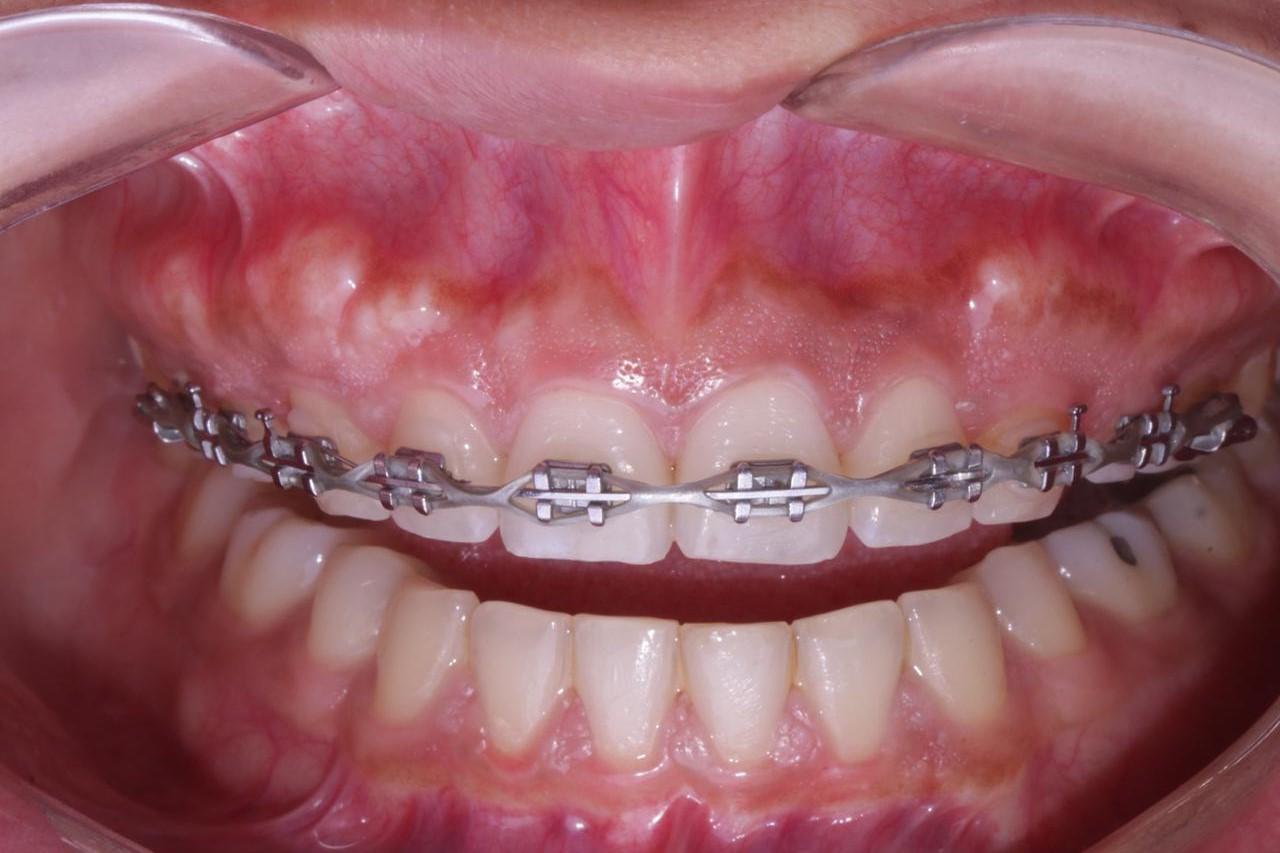

ANTES

antes Exceso de hueso y de encía despues Exceso de hueso y de encía

Después de tratamiento de ortodoncia presenta exceso de hueso y encía.